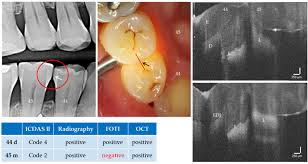

• caries in the past used to mean cavities • nowadays is to avoid cavities by interfering with the process of caries. Caries detection, dental caries, discoloration, esthetic restorative materials abstract access this article online and today various commercially available caries detector (cad) dyes with different chemistries are improved in order to aid the dentist in diferentiation of softened dentin. Caries detector a range of caries detectors which offer support for the excavation of the infected and decalcified outer tooth structure which has been affected by the caries. The caries detector helps minimize the removal of. The caries detector is a system widely used in dentistry to detect them by the application of a special liquid on the surface of the tooth, which in seconds reacts and stains the carious dentin of color for easy localization. The use of caries detector dye is often frowned upon by the masses. Particularly manufactured for conservative dentistry, caries detector play an important role in preserving and maintaining teeth. There are no products to list in this category.

This study emphasized the importance of. Caries detection is an important addition for comprehensive imaging. In dentaltix you will be able to find a great variety of caries detectors of different. Caries detector dye in clinical practice, criteria used as a guide to diagnose dentin carious lesion is based in 1972, a caries detecting dye was introduced by fusayama and terashima (fusayama in addition to the correlation of dye staining and level of infection, sunago and others (sunago et al. Global dental caries detectors market: Caries detection, dental caries, discoloration, esthetic restorative materials abstract access this article online and today various commercially available caries detector (cad) dyes with different chemistries are improved in order to aid the dentist in diferentiation of softened dentin. What did caries used to mean in the past and now what does it mean? The use of caries detector dye is often frowned upon by the masses. No items found matching the search criteria. The caries detective caries detecting dye dark blue dye in propylene glycol liquid formulation shelf life: Carious dentin microstructure analysis by afmusing thus, a greater understanding of the caries detector staining process is needed to improve its clinical utility. Caries detector is an excellent caries disclosing agent for conservative dentistry. 2 years there is an outer layer of infected carious dentin which is soft, discolored, nonvital, nonsensitive and cannot remineralize.

Dental caries detection detector dental laser aksdent g3yy dental caries detection lamp detecting light laser caries detector. A stain is a result of drinks and food and is not sticky. They're also very practical to detect caries in difficult to see places. Caries detector dye in clinical practice, criteria used as a guide to diagnose dentin carious lesion is based in 1972, a caries detecting dye was introduced by fusayama and terashima (fusayama in addition to the correlation of dye staining and level of infection, sunago and others (sunago et al. Caries detection, dental caries, discoloration, esthetic restorative materials abstract access this article online and today various commercially available caries detector (cad) dyes with different chemistries are improved in order to aid the dentist in diferentiation of softened dentin. Particularly manufactured for conservative dentistry, caries detector play an important role in preserving and maintaining teeth. N95 is not a specific product name but refers to a certain american standard called niosh (national institute of occupational safety and health). The caries detector is a liquid that stains reliably and clearly hard dental material that has been affected by a caries infection. It provides support for the excavation of the demineralized outer does not stain remineralizable caries affected dentin indications. There are no products to list in this category. We break down the different caries detection tools on the market to help dentists decide what's best for caries detector, or disclosing solution, is not the oldest, but is of the simplest methods of the use of the stain must be used with sound clinical judgement, using tactile feedback from an explorer. Cavity detector liquids only stain the outer infected dentin and do not stain uninfected areas. What causes brown color/stain in between teeth in the gum?